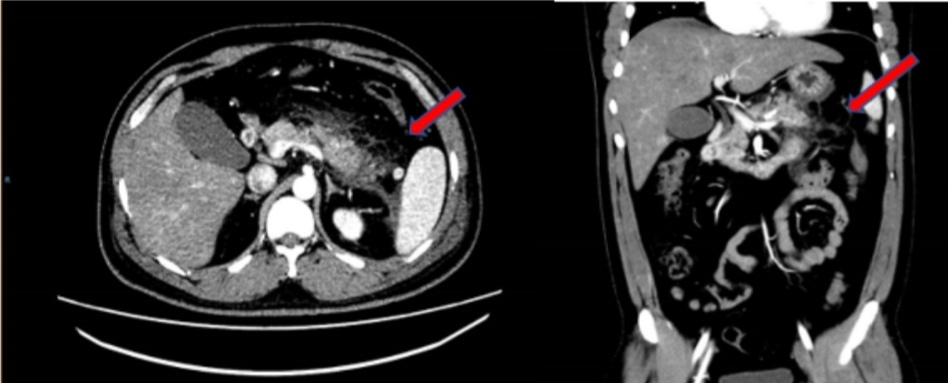

腹部增强CT提示胰腺尾部肿胀,胰腺周围脂肪间隙模糊,多发斑片状、条索影。红色箭头示胰腺脂肪间隙。